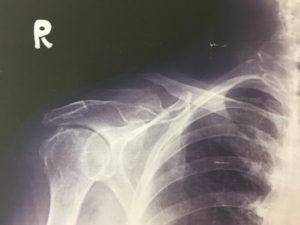

さて、今回は『鎖骨骨折』について、紹介させていただきます。

それは鎖骨の形状にあります。鎖骨はS状の骨でありその曲がっているところに力が集中してしまうからです。そのため骨の丈夫な方でも骨折してしまうのです。

一般的には、大きな衝撃により起こるといわれ、スポーツや運動中の転倒で起きやすいです。また、骨粗しょう症などで骨がもろくなってしまっている場合には、軽い転倒でも骨折してしまいます。

鎖骨骨折はずれを生じることがほとんどであるため、適切な処置を行わなくてはいけません。自己判断でそのままにしていると、手にシビレが出たり、手が挙がらなかったりと後遺症が残ってしまいます。